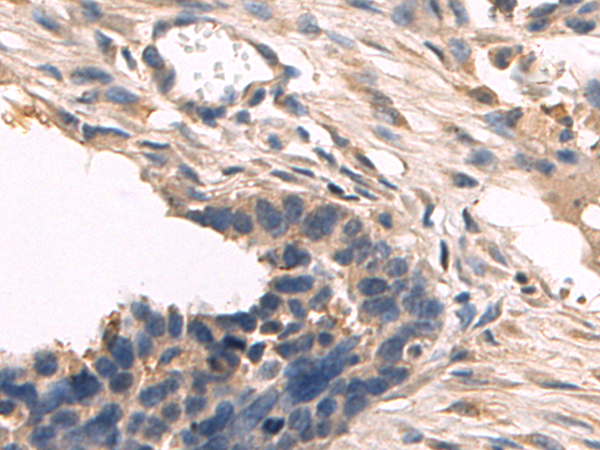

分类: 科研抗体货号: P08321别名:应用: IHC反应种属: Human, Mouse, Rat